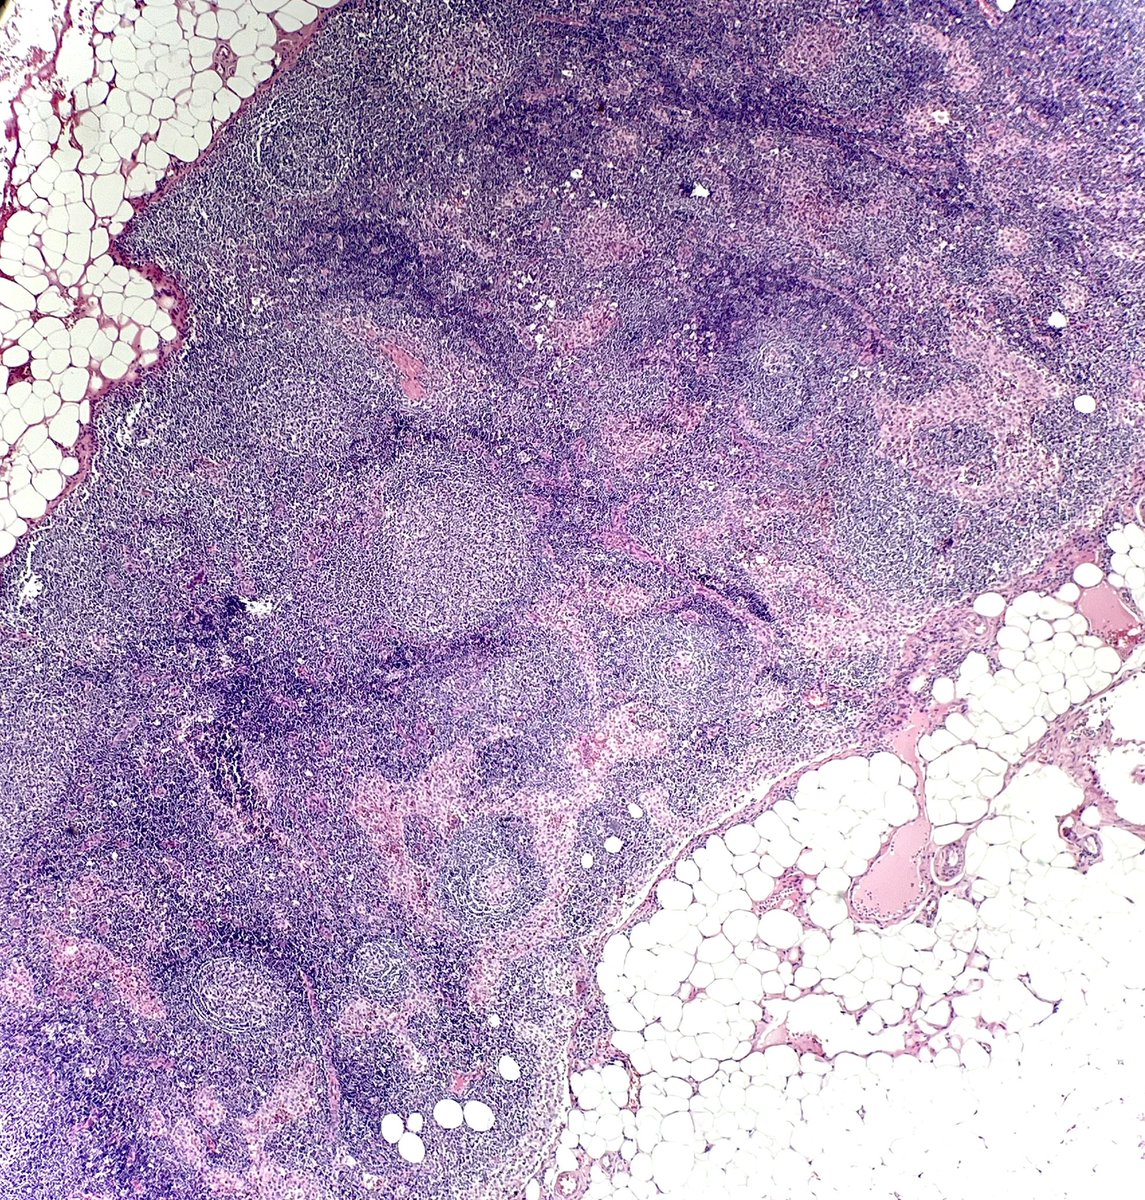

Tiny tiny lymph node that looked a little bit monotonous… what would you call it? #hemepath #PathTwitter @kirillkarlin

NanaMatsumoto8's tweet image. Tiny tiny lymph node that looked a little bit monotonous… what would you call it?  #hemepath #PathTwitter @kirillkarlin